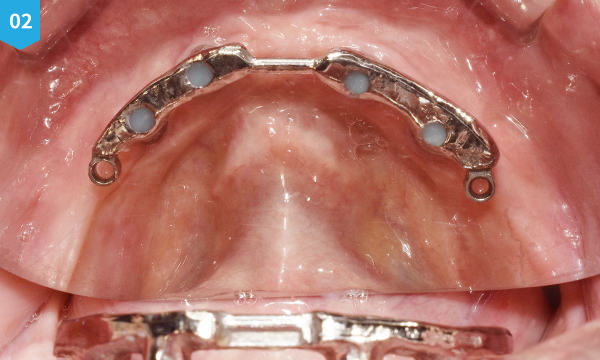

Bar type 임플란트 틀니는 윗턱에는 임플란트를 6개, 아래턱에는 4개를 심어 금속으로 된 바를 입안에 고정시킨 후, 그 Bar에 틀니를 결찰 하는 고정력이 우수하며 통증이 없는 틀니입니다.

불편한 착용감과 고정력이 약한 기존에 틀니와는 다르게 잇몸 안에 임플란트를 심은 후 특수 제작한 금속 바에 틀니를 창작하여 고정력이 매우 우수합니다. 또한, 바(bar)에 장착된 틀니는 통증이 없으며, 인중이 많이 주저 않아 나이 들어 보이시는 분들에게 심미적인 개선 효과도 기대할 수 있습니다.

위턱과 아래턱에 임플란트를 심은 후 환자 구강 상태에 맞춰 원내 기공소에서 직접 제작한 바를 입안에 고정시켜 통증 없이 편한 착용감에 틀니를 만족스럽게 사용하실 수 있도록 시술합니다.

바(Bar) 착용 모습